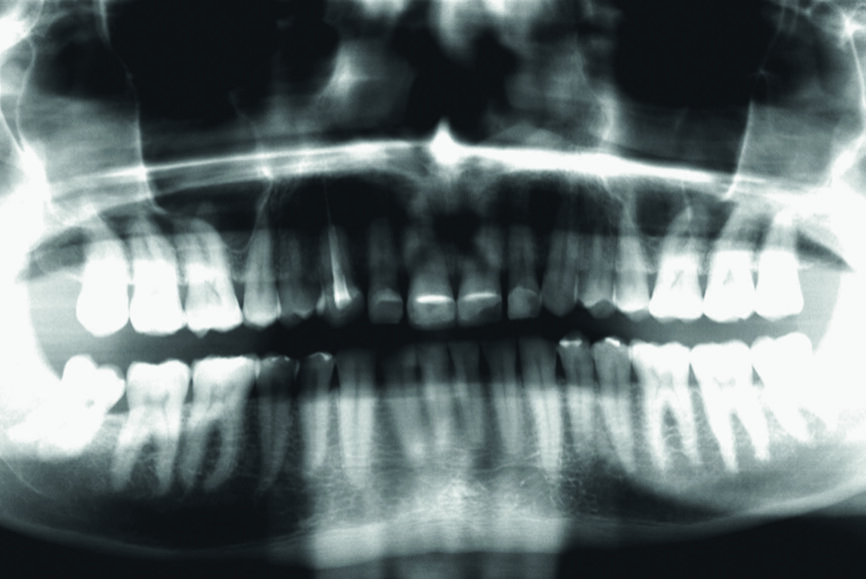

En 2015, un patient de 47 ans se présente au cabinet en raison d’une douleur au niveau de l’ATM. Il a également une préoccupation d’ordre esthétique, car une partie de la facette posée sur l’une des incisives centrales supérieures est fracturée (Figs. 1–3). L’analyse clinique et radiographique (Fig. 4) indique une perte de DVO et de substance dentaire dues au bruxisme.

Fig. 4 : Situation initiale, radiographie panoramique (2015).

Fig. 15 : Radiographie panoramique à la fin du traitement.